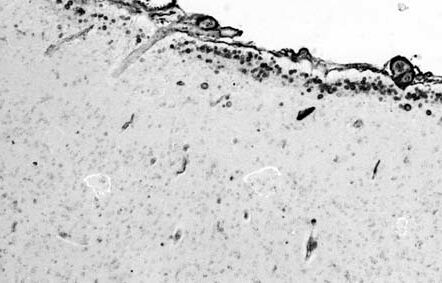

The corpora amylacea were found mainly in the sub-pial and ependymal regions and thinly in the hippocampal formation, white matter of the cerebrum and cerebellum, and/or brainstem from aged individuals. The large number of corpora amylacea (3+ score in Table 3) was observed in the hippocampal formation from 2 patients with Alzheimer type dementia (74 year-old, male and 76 year-old female), 2 patients with dementia with neurofibrillary tangles (82 year-old female and 83 year-old male) and two patients with Down's syndrome, and thinly found in the sub-pial and ependymal regions of the hippocampal formation from 7 patients with schizophrenia and 12 of the controls.

![]() |

HE, PAS, AB and AF stains, and most of corpora amylacea appeared to be clearly and strongly shown by lectin staining using GSA-I-B4, UEA-I, DBA (Fig. 1C), and other lectins stained all of the corpora amylacea.